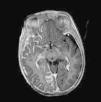

Brain Magnetic Resonance ImagingBrain MRI with gadolinium enhancement is the imaging technique of choice for diagnosis of SWS.28 With this technique, it is possible to visualize the leptomeningeal vascular malformation that confirms diagnosis of SWS (Fig. 7). Calcifications in MRI can also be detected in T2 sequences as images of cortical and juxtacortical hypointense signal. MRI can also detect abnormal venous drainage, reduced brain volume, enlarged ipsilateral choroid plexus, prominence of subependymal and medullary veins, loss of volume of the affected brain hemisphere, and accelerated myelinization underlying the leptomeningeal angioma.14,24,37 These changes are more evident after 1 year of age.38